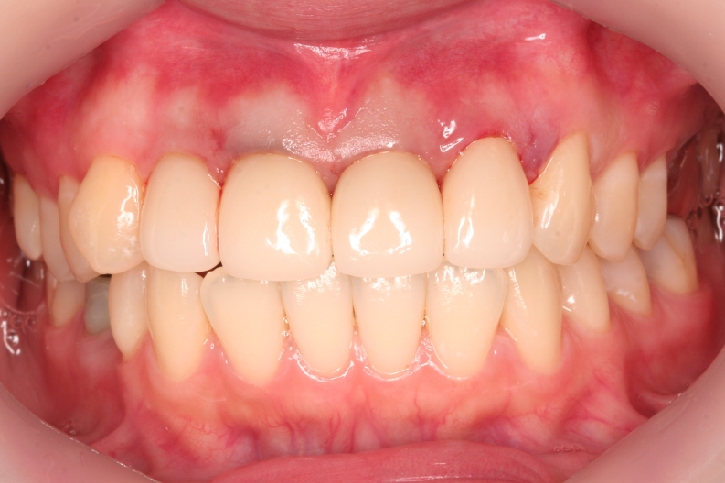

メタルセラミックス修復

担当歯科医師:川津良介理事長

2013年5月3日平成25年5月2日 千葉市中央区 H.S様 右下67番 メタルボンドクラウン修復